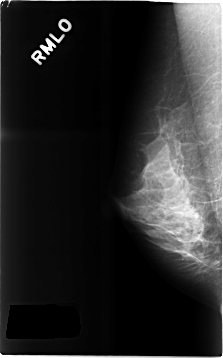

C_0300_1.RIGHT_MLO

RIGHT_CC LINES 4632 PIXELS_PER_LINE 2928 BITS_PER_PIXEL 12 RESOLUTION 50 NON_OVERLAY

RIGHT_MLO LINES 4648 PIXELS_PER_LINE 2896 BITS_PER_PIXEL 12 RESOLUTION 50 NON_OVERLAY